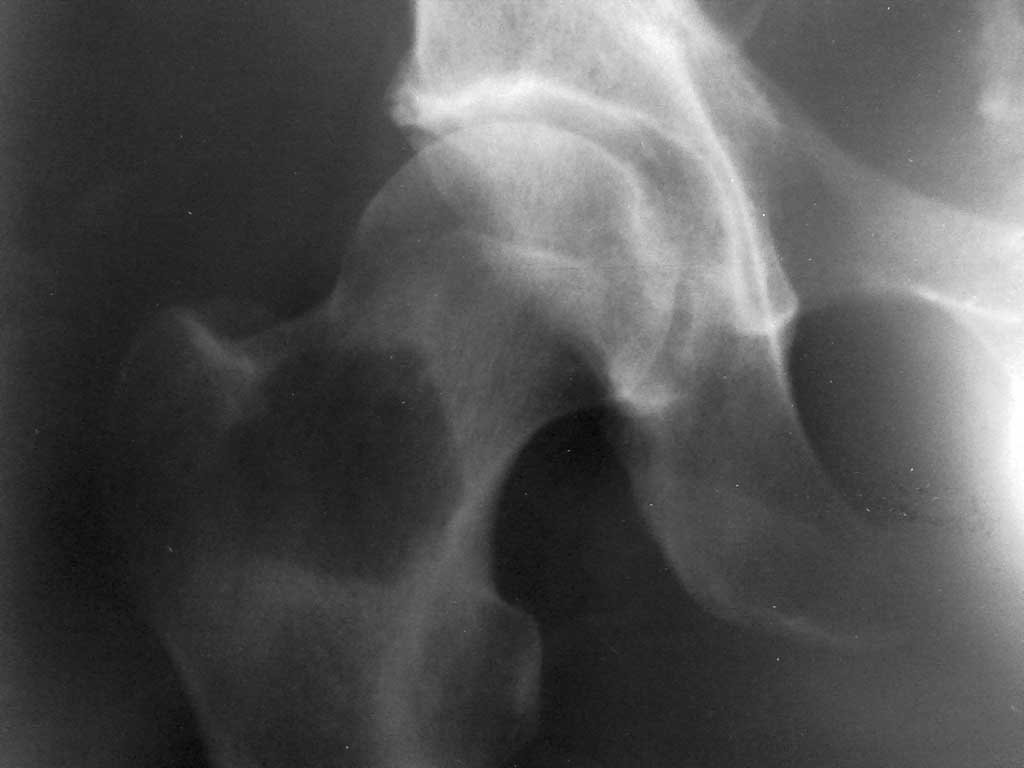

у пациента 54 лет, прооперированного в марте 11г. по поводу рака левого легкого имеется

выраженный болевой синдром в области тазобедренного сустава справа. госпитализирован для

дообследования. выявлено новообразование вертельной области. прошу Ваших мнений по

тактике лечения. Других метастазов не выявлено. пациент хочет лечиться.